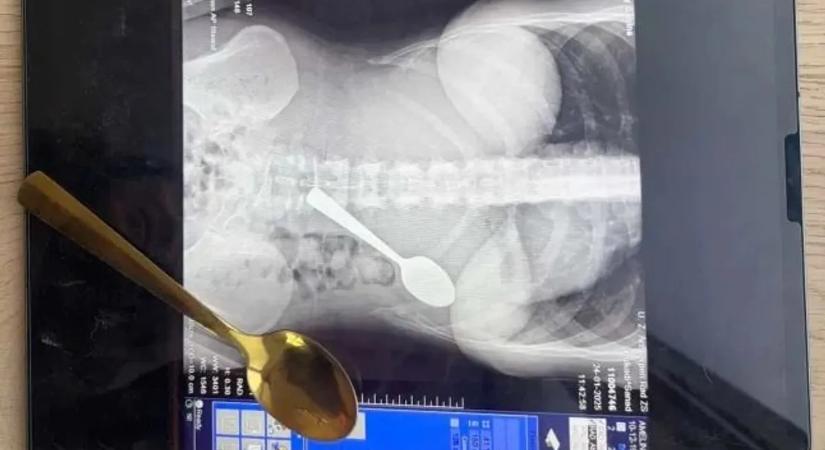

Az orvosok szedték ki a gyomrából a 17 centis evőeszközt.

Hihetetlen baleset: lenyelt egy kanalat a nő, hogy ne fulladjon meg